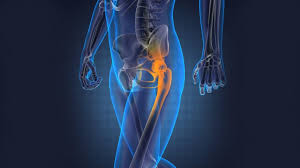

Hip revision (a repeat hip replacement) surgery involves replacing your artificial hip joint if it's become loose, infected or worn out. Hip replacement surgery can be performed as a total replacement or a hemi (half) replacement. Alternatives to hip replacement surgery include conservative management, hip resurfacing, hemiarthroplasty, and viscosupplementation. Hip replacement surgery involves replacing the hip joint with new artificial joint parts. Hip replacement surgery and hip resurfacing are often the only surgical options presented to a patient to deal with their debilitating pain, though hip the innovative regenexx procedures restore hip function and mobility and decrease pain without the need for surgery by regenerating damaged. Direct anterior total hip replacement surgical procedure video. The most common conservative alternatives to hip replacement surgery are assistive devices (canes or walkers) to reduce stress on the affected hip there are both surgical and nonsurgical options to treat a herniated disc. Statistics and hip replacement therapy. Surgery and increase hip function. Some joint preservation procedures are newer and considered experimental, dr. A hip replacement procedure is a major surgical operation that is usually only reserved for cases where alternative therapies have failed. Hip replacement surgery is one of the most successful modern orthopedic surgical procedures. Lifestyle and medical options can help reduce discomfort and slow the damage.

Learn about hip replacement surgery, total hip replacement and partial hip replacement. Before opting for knee replacement surgery, it's important to consider all your options. Last updated may 24, 2019by howard j. Nonsurgical treatments include medication and going to a chiropractor. There is an alternative type of surgery to hip replacement, known as hip resurfacing. Hip replacement surgery can be performed as a total replacement or a hemi (half) replacement. Have you considered all the hip replacement alternatives available? Knee assessment and hip mechanics online course: Hip replacement surgery involves replacing the hip joint with new artificial joint parts. Some examples of the alternative approaches to treating damaged or painful hips are described below. Hip replacement is a surgical procedure in which the hip joint is replaced by a prosthetic implant, that is, a hip prosthesis. How long you stay in the hospital or surgical center after your surgery depends on many factors, including your overall health. Hip replacement surgery removes damaged of a hip joint & replaces them with new parts.

Lifestyle and medical options can help reduce discomfort and slow the damage. Hip replacement surgeries use modern biomaterials. Hip replacement surgery removes damaged of a hip joint & replaces them with new parts. Hip replacement surgery is one of the most successful modern orthopedic surgical procedures. Nonsurgical treatments include medication and going to a chiropractor. Hip resurfacing surgery is an alternative to standard hip replacements for patients with severe arthritis. The difference lies in the way it is because the surgical exposure, preparation of bone, and placement of the component with cement may cause this bone to be more vulnerable. Conservative management, which is aimed at delaying the need for surgery and, in a few cases may be sufficient for you to manage for many years. Alternatives to hip replacement surgery include conservative management, hip resurfacing, hemiarthroplasty, and viscosupplementation. In a hip resurfacing surgery, the implant is smaller, and less normal bone is removed. Some examples of the alternative approaches to treating damaged or painful hips are described below. Before opting for knee replacement surgery, it's important to consider all your options. Hip replacement may be an option if your hip pain interferes with daily activities and nonsurgical treatments haven't helped.